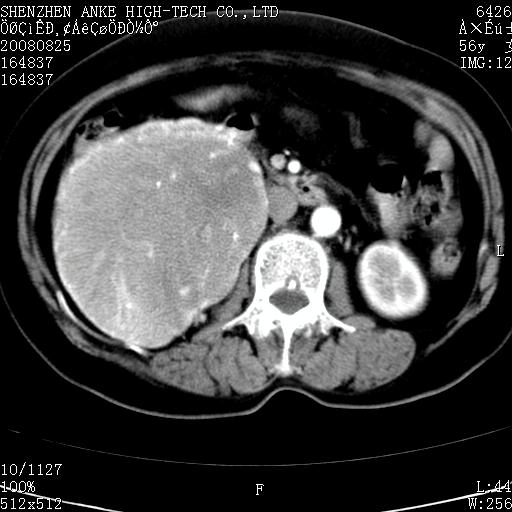

患者,女性,56岁,腰痛3年,查:右腹部约8x10cm肿块,固定,无压痛;8月23日在外院做了平扫,发现右肾巨大肿块(外院具体诊断不祥);今天在我院做了静脉肾盂造影,示:右肾明显增大,分泌功能明显减弱。

1)考虑右肾癌并右肾静脉瘤栓形成。2)脂肪肝。